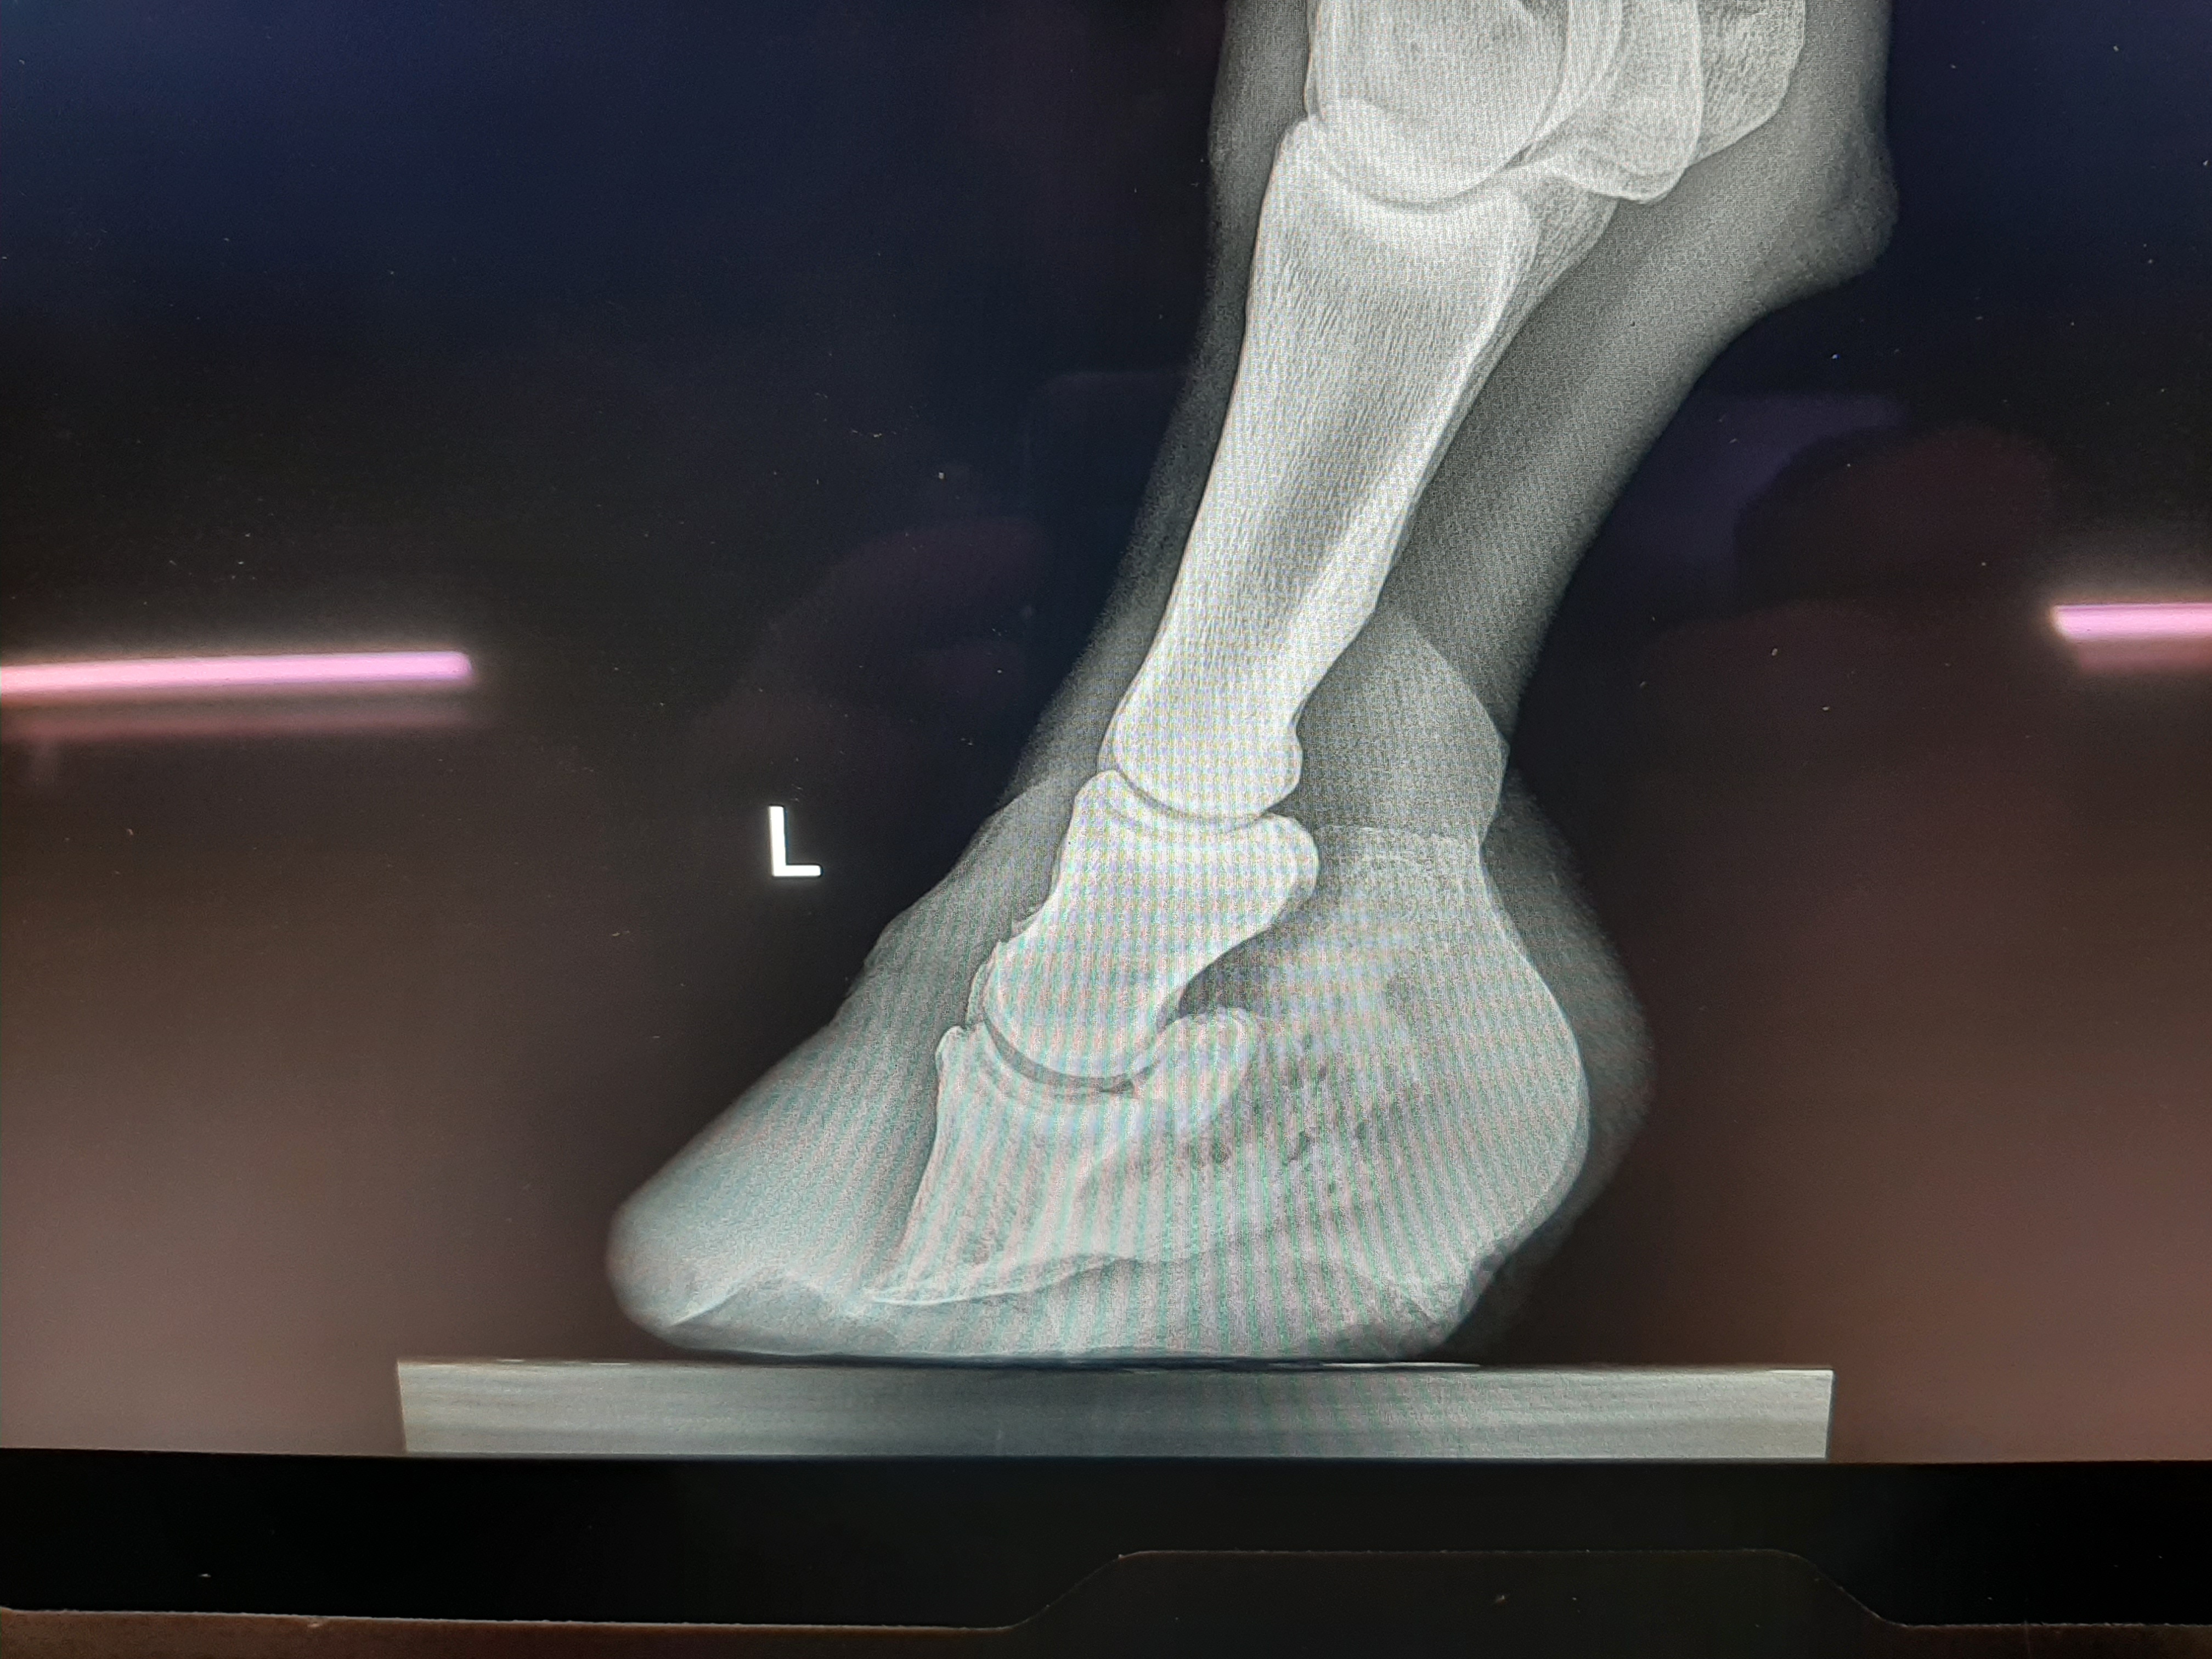

Founder/ Laminitis Case

Before adjustment of hoof. ——– After adjustment of hoof.

This is an example of a founder/ laminitis case that I have been working on. The photos on the left show the beginning of the hoof when I saw it. The photos on the right are after the trim with other x-rays to show the amount of more hoof wall and sole I would have left to take off. Besides the hoof capsule showing that the foot was in bad shape the x-rays show that the coffin bone / P3 is pointed in a downward direction to much. It needs to be pulled back up to go along in the same direction as the outer edge of the hoof wall. Unfortunately horses in this kind of shape are hard to recover to a sound enough shape to be ridden.